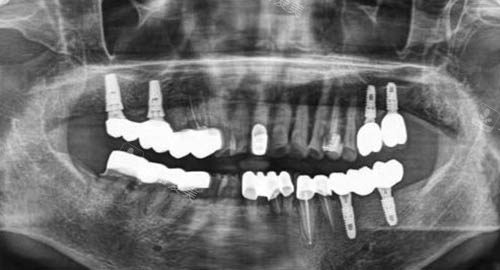

多颗牙齿种植ct

它采用智能化种植技术,这种较高的技术能够实现更更准一些的定位。

在传统的种植牙过程中,可能会存在一定的误差,而智能化种植借助较高的设备和系统,可以精细分析患者口腔的各项数据,包括牙槽骨的密度、高度、宽度等,从而确定更佳的种植位置和角度。